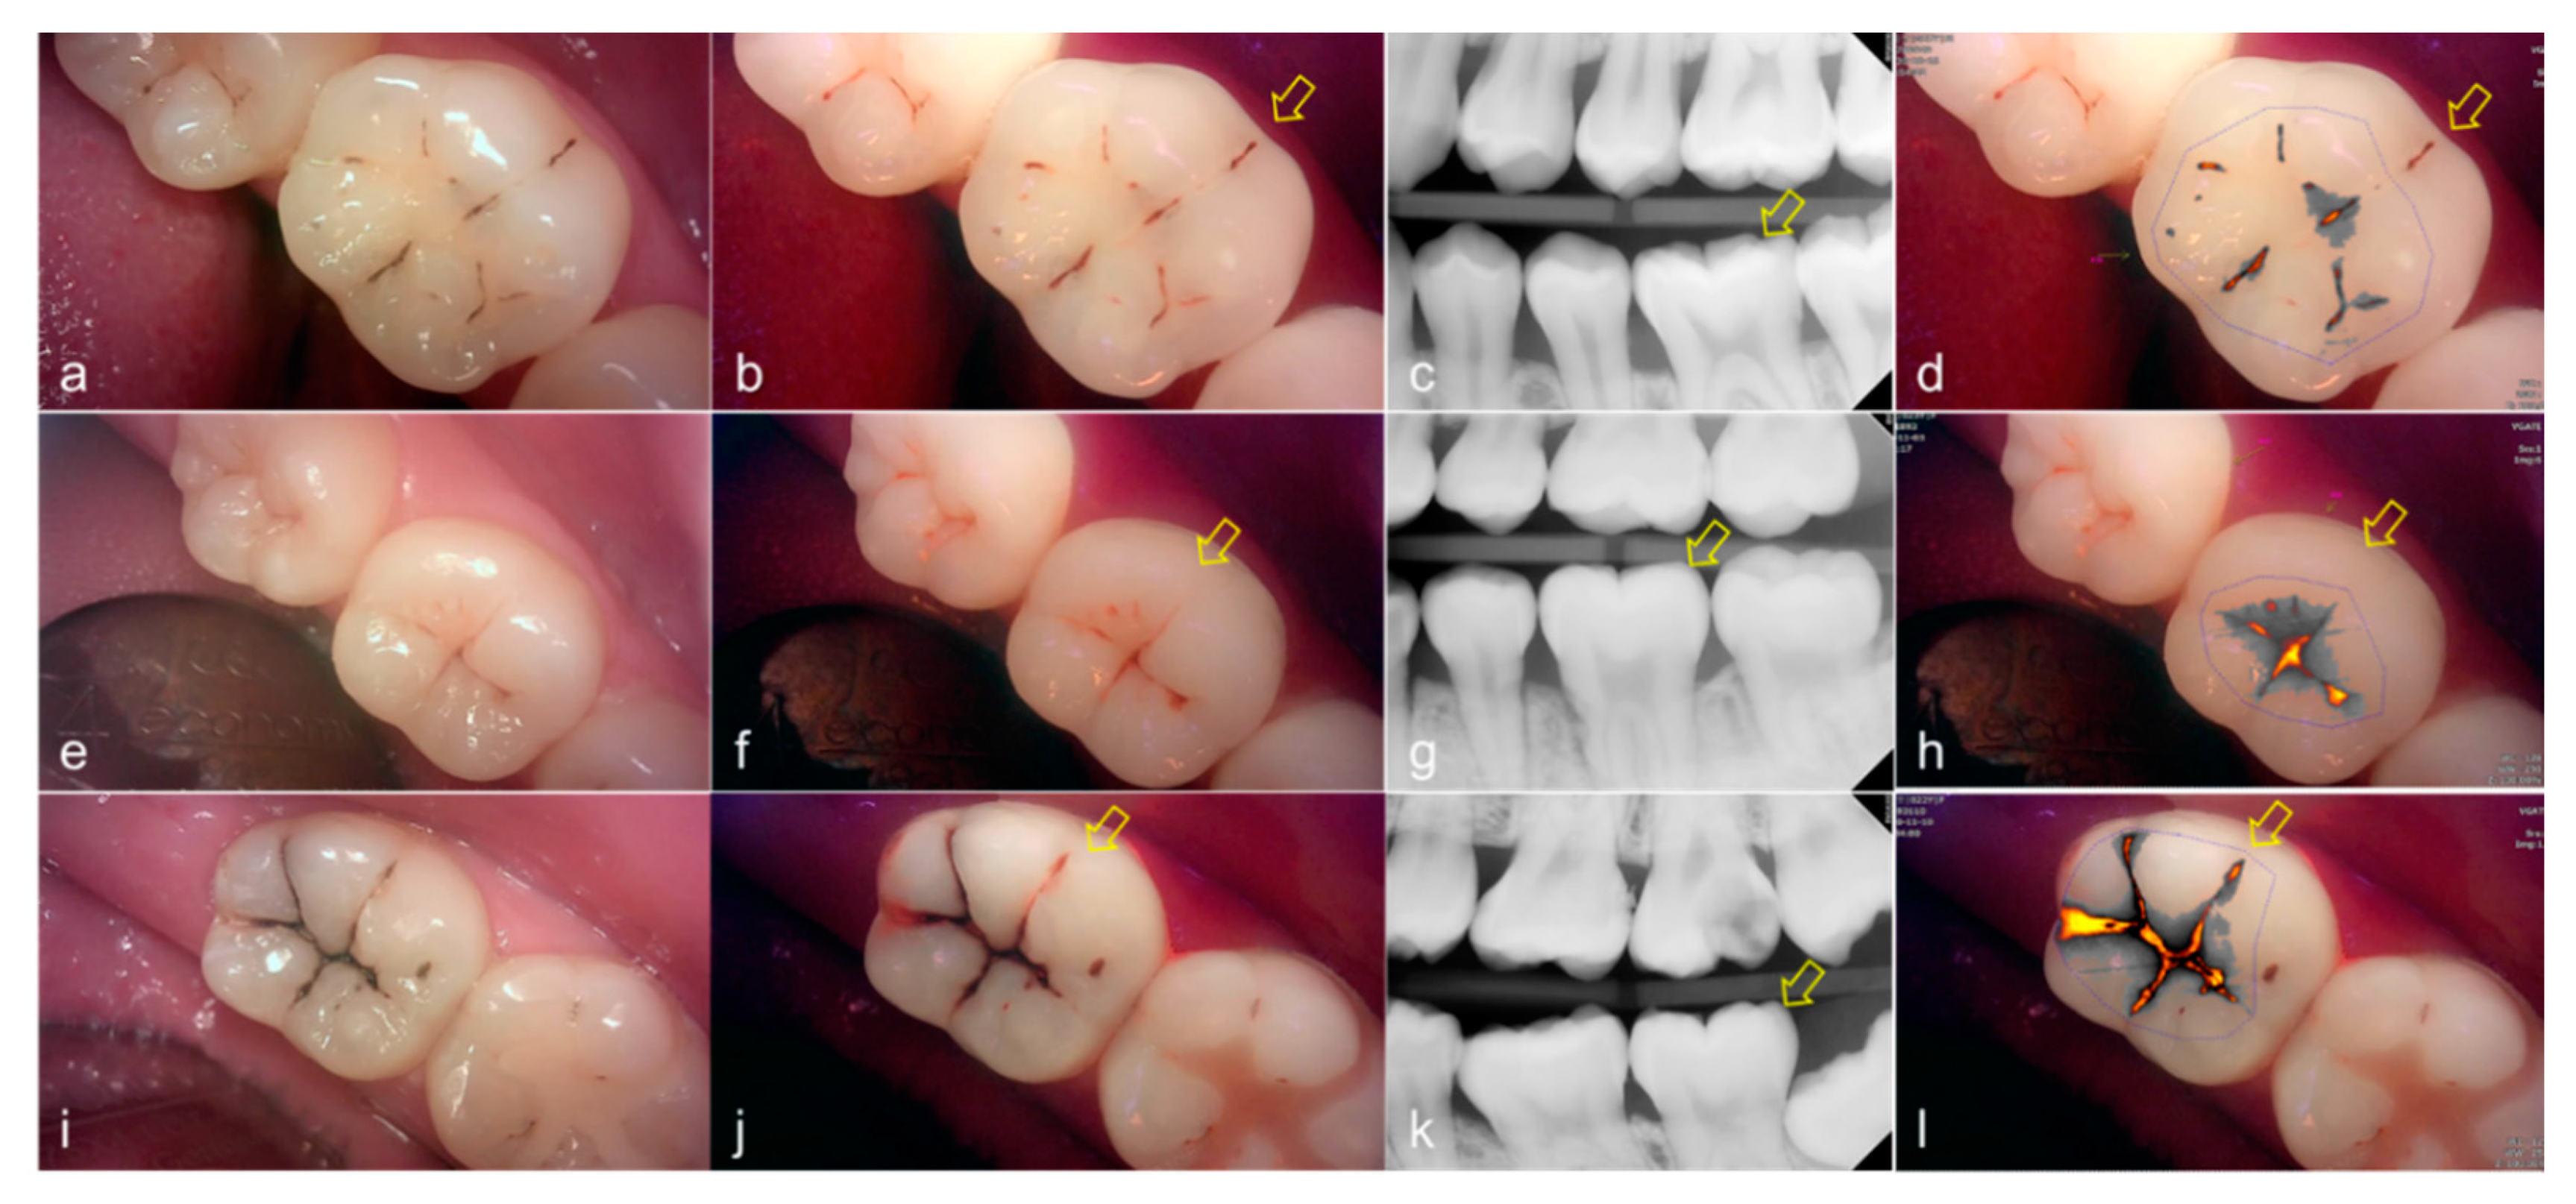

The values of the QLF parameter according to the value classified based on the QLF criteria were significantly different (Table 2). The cut-off value of |ΔFmax| and ΔRmax for determining a crack (QLF criteria scores 0 and 1 vs. 2) was 20.80 and 39.00, respectively. In addition, the AUROC of QLF parameters were similar (0.83, 0.82) (Table 3). Representative images of QLF and bitewing radiograph of dental cracks are shown in Figure 9 and Figure 10.

Figure 10.

Cracks: (a–d) QLF caries score 2 (fluorescence loss and red fluorescence glow extending around crack site) and visual examination score 0 (no detectable crack line) on #25; (e–h) QLF caries score 2 (fluorescence loss and red fluorescence glow extending around a crack site) and visual examination score 1 (ambiguous detectable crack line) on #17 (arrow 1), QLF caries score 1 (fluorescence loss and red fluorescence present as a line in the crack site) and visual examination score 0 (no detectable crack line) on #17 (arrow 2); (i–l) QLF caries score 2 (fluorescence loss and red fluorescence glow extending around a crack site) and visual examination score 2 (distinct detectable crack line) on #47; (a,e,i): white-light image of QLF; (b,f,j): fluorescence image of QLF; (c,g,k): bitewing radiograph; (d,h,l): analyzed QLF image using QA2 software.